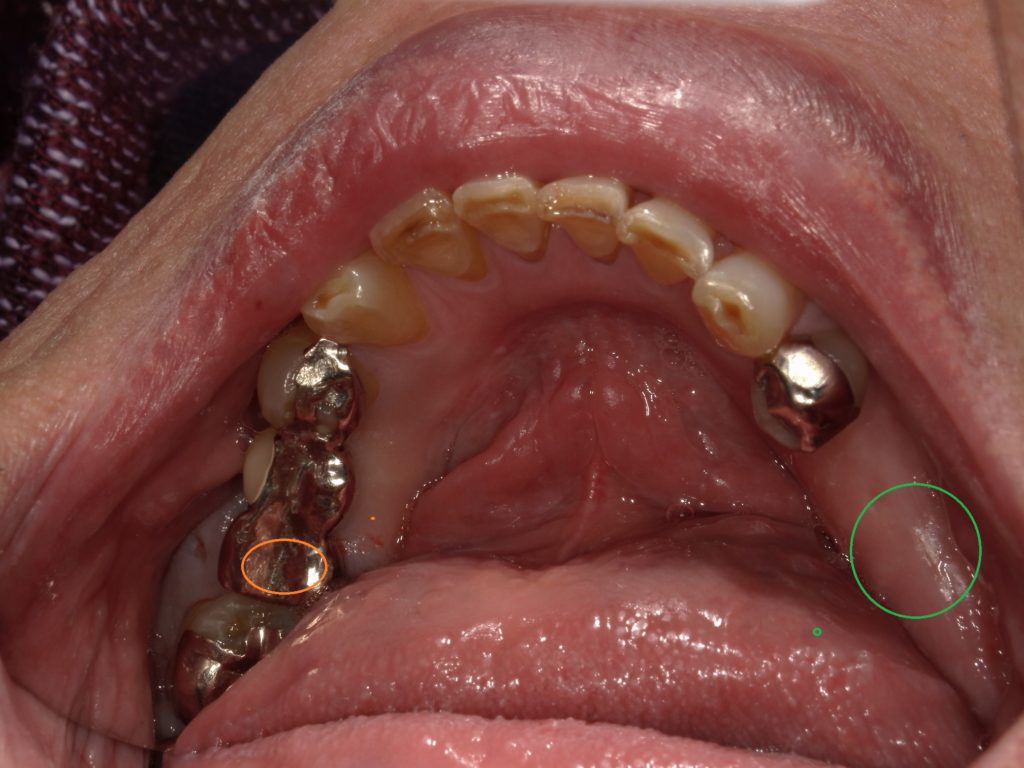

いくつかのブリッジのトラブル画像をお見せします。

非常に無理のかかった設計です。

オレンジの丸の部分が今回割れて抜歯となりました。

緑の欠損した部位に歯を入れずに食べていてさらなる欠損を起こしています。

この様に欠損がさらに欠損を生むことは日常の診療で多々散見される悲しいケースです。

最初に経験する欠損をどのように対処するかが、その後のお口の状態を大きく左右します。